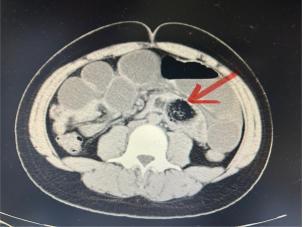

接诊的王东海医生详细询问了小宇的饮食情况和症状,并做了腹部CT,结果很快明确了:粪石性小肠梗阻。CT显示,小宇的小肠里有明显的团块状阴影,肠壁水肿,肠腔也扩张了。王医生解释说,一下子吃了太多春笋,那些粗纤维消化不掉,在肠道里积在一起,形成了一个硬邦邦的“粪石”,导致肠道内容物无法正常通过。